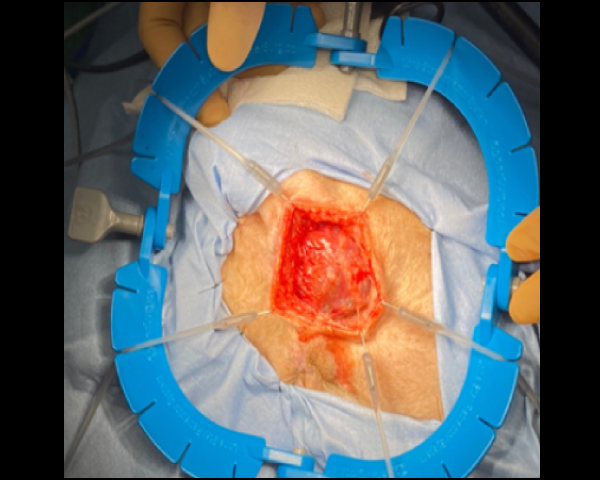

リトラクターリングを用いてアポクリン腺癌の摘出